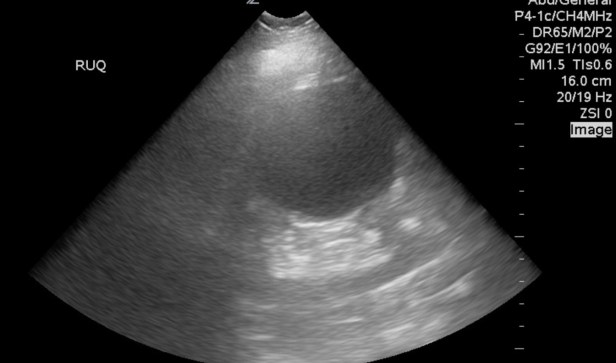

Scanning the right upper quadrant of the abdomen sees what he/she thinks is a AAA, but actually is a large renal cyst. Make sure to scan the structure in it’s entirety in two planes. Also, decrease your depth and gain.